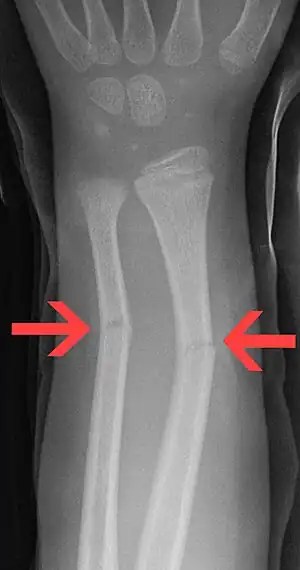

| Greenstick fractures of the mid radius and mid ulna on X-ray. | |

Greenstick fracture is type of break, where one side of the bone is disrupted and the other bends.[2] They occur most commonly in the first 10 years of life.[1] Symptoms generally include pain and a decreased ability to move the affected area.[1] Complications may occasionally include nerve injury.[1] Typically bones of the forearm or arm are involved; though, the leg, collar bone, or less often other bones may be affected.[1]